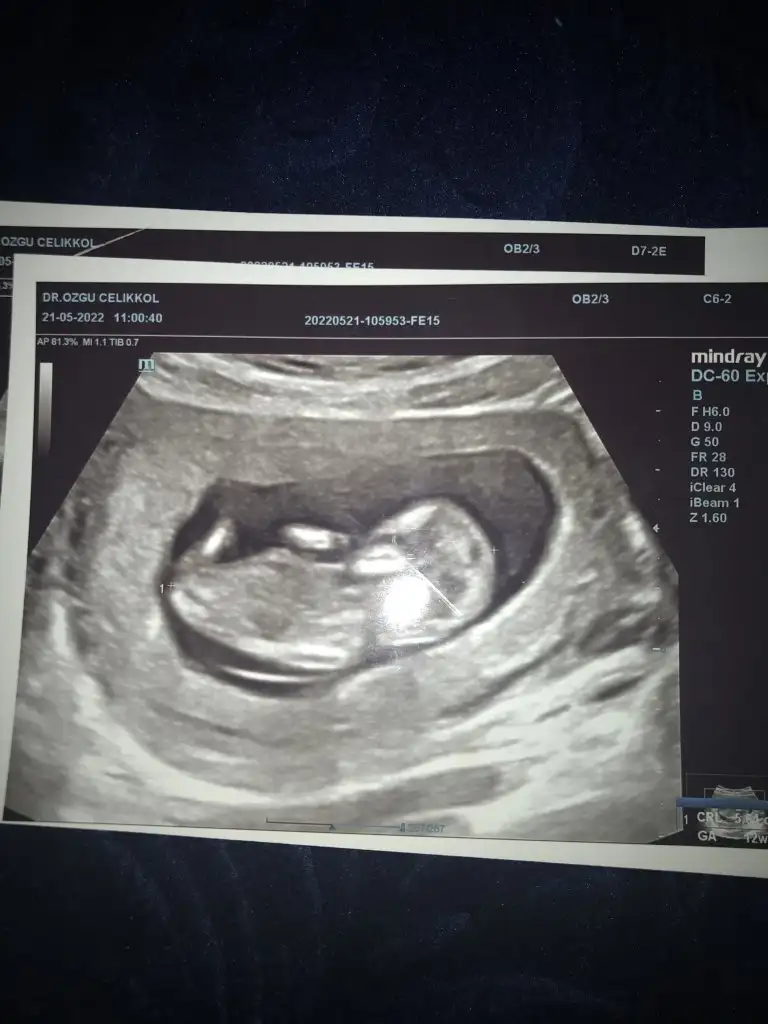

Üsteki erkek altaki kız gibi sanki emin olamadımslm 12 haftalık ikiz gebelik banada tahminde bulunabilirmisniz

Merhabalarnasılsınız. Bir tahmin de ben rica edebilir miyim. 11-12 haftalik.